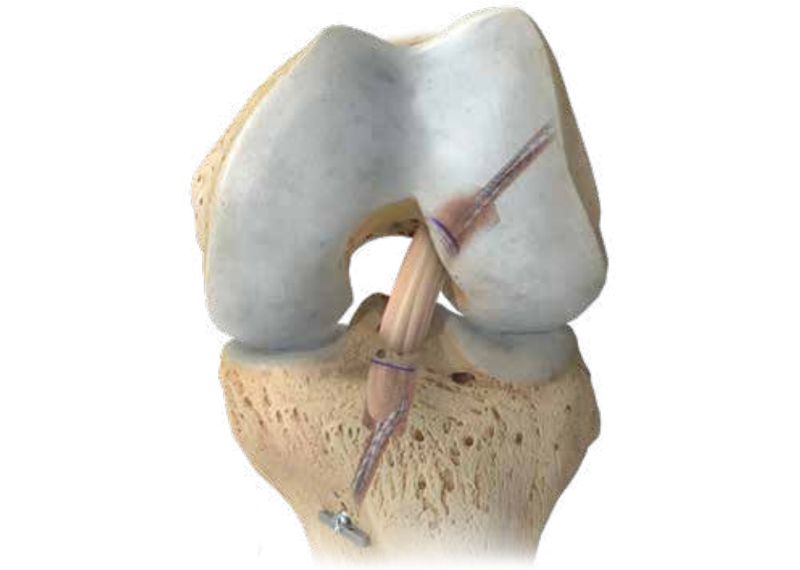

Poškodba križne vezi

Rekonstrukcija križne vezi